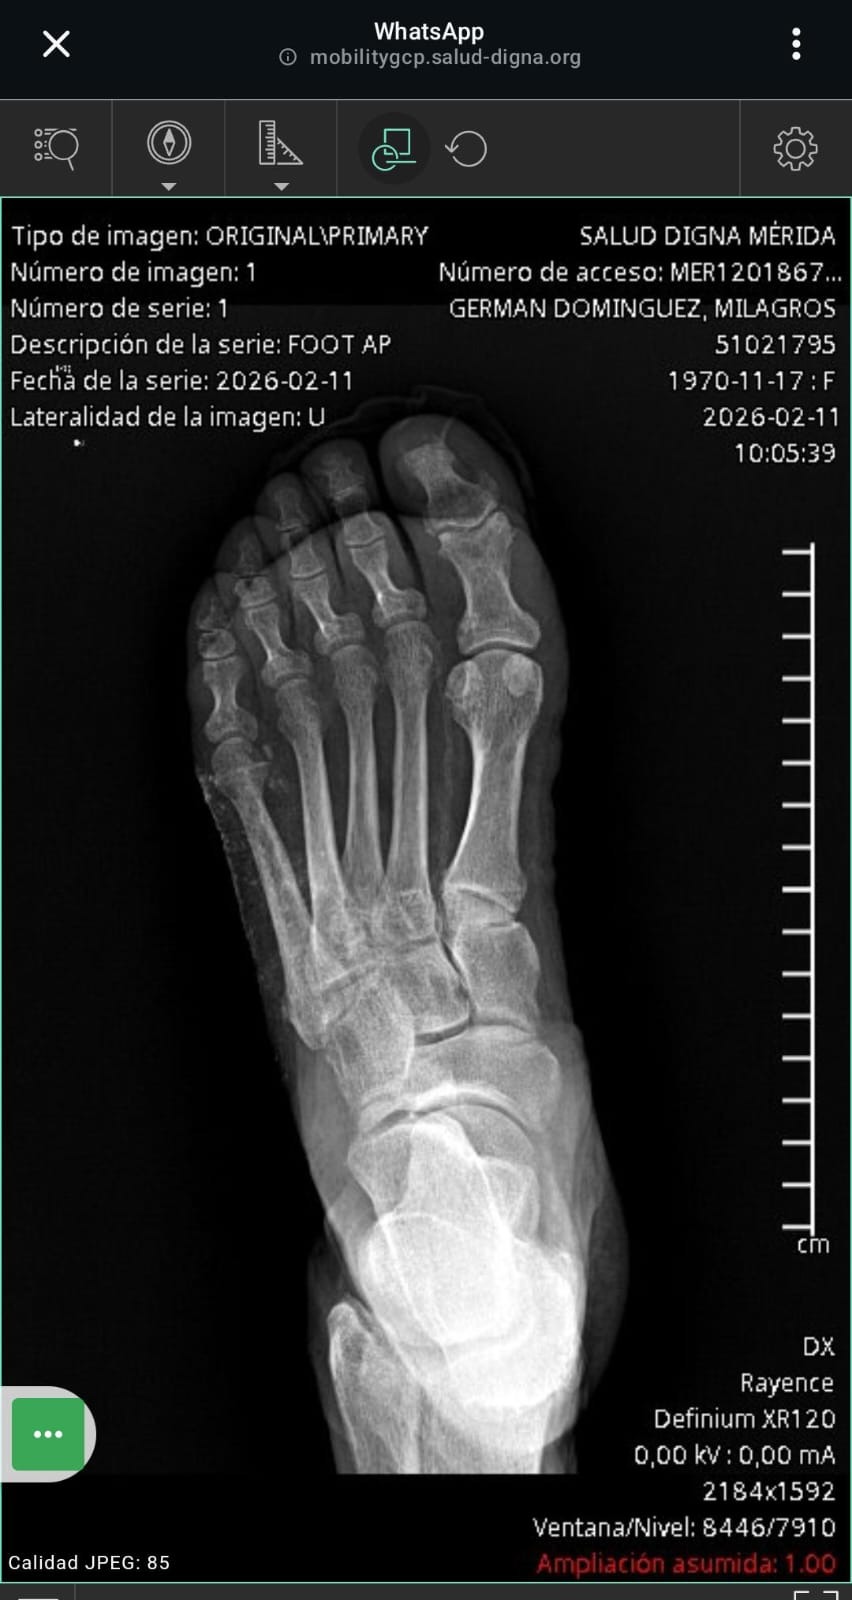

Milagros Germán, está pasando por una situación increíblemente difícil. Milagros es diabética y, mientras trabajaba para ayudar a cubrir sus gastos, desarrolló una ampolla en el pie. Lamentablemente, debido a complicaciones de la diabetes, la situación se ha vuelto muy grave. La última noticia es que necesitará una amputación de la pierna por debajo de la rodilla. Esta noticia ha sido devastadora para ella y para nuestra familia.

Milagros Germán is my husband's niece, and she lives in Mexico. Right now, she is going through an incredibly difficult time. Milagros is diabetic and, while working to help cover her expenses, she developed a blister on her foot. Unfortunately, due to complications from her diabetes, the situation has become very serious. The latest update is that her leg will need to be amputated below the knee. This news has been devastating for her and our family.